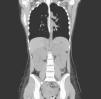

Ecografía renal: Aumento de tamaño de ambos riñones que miden 14 y 15cm de diámetro longitudinal (fig. 1).

TC toraco-abdominal: únicamente se confirma nefromegalia bilateral sin otros datos patológicos (fig. 2).